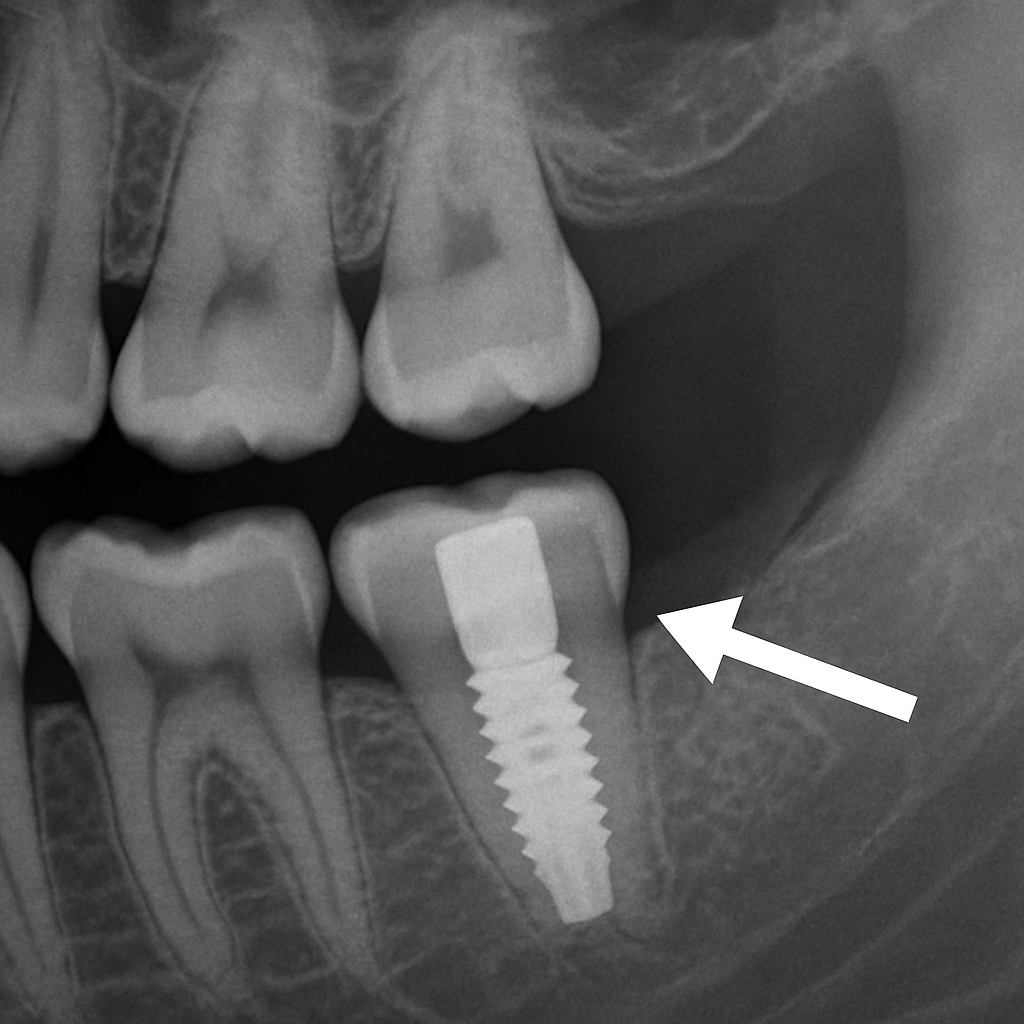

Dental implants

An implant replaces the root and the tooth with a post, abutment, and crown. Implants preserve bone, feel and function like natural teeth, and don’t harm neighboring teeth. For many people who want a long-term solution, an implant is the best way to replace a missing tooth.

How Dental Implants Are Placed

Implant placement starts with planning: scans and models help map the site. The implant post is placed into the jaw, then a healing period allows osseointegration (bone fusing to the implant). After healing, an abutment and crown are attached. Most patients have mild discomfort and return to normal activities in a few days; full healing takes a few months.